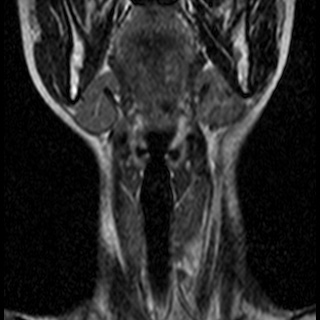

Невринома множественная шейного отдела с врастанием в спинно-мозговой канал

Здравствуйте! Мне 27 лет. Я стала жаловаться на головокружение, головные боли, пульсирование в голове. После исследования мрт выявилась следующая патология . Документы предоставляю. Можете ли Вы помочь в этой патологии? Как попасть к Вам на консультацию, учитывая эпидемиологическую обстановку? Спасибо.